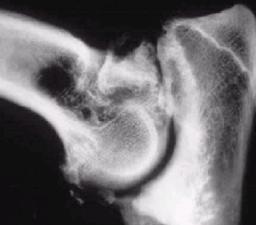

CAZUL nr. 18

Istoricul bolii

Câine: 11 luni mascul, rasă Ciobanesc german.

Debutul bolii în urmă cu 2-3 saptamâni. Animalul schiopăta de piciorul stâng anterior. schiopatura este permanentă.

S-a apelat la medic care timp de o saptamână a administrat antiinflamatorii. În perioada tratamentului s-a observat o foarte usoara (neglijabilă) îmbunatatire, dupa care schiopatura a revenit.

Examen clinic

Temperatura 38,6oC, Frecventa cardiacă 118, Frecventa respiratorie 16

schiopatura de gradul I-II (pasi mici, rigizi si o evidentă limitare a miscarilor de flexie si extensie a cotului). Usoară tumefactie a articulatiei cotului.

Manipularea membrului cu producerea unor miscari de hiperflexie-hiperextensie produce constant durere, În timpul hiperextensiei articulatiei cotului crepitatia si durerea sunt bine evidentiate.

Cerinte suplimentare – examen radiologic – articulatia cotului

Întrebari – exista antecedente traumatice? – daca aceste antecedente traumatice nu exista, este posibila existenta unei nonuniuni la nivel ulnar (în acest caz a procesului anconat al ulnei) si se cere si radiografia articulatiei cotului de la membrul stâng (sanatos). Chirurgia ortopedica a animalelor de companie, pag. 334.

Diagnostic fractura de proces anconat al ulnei